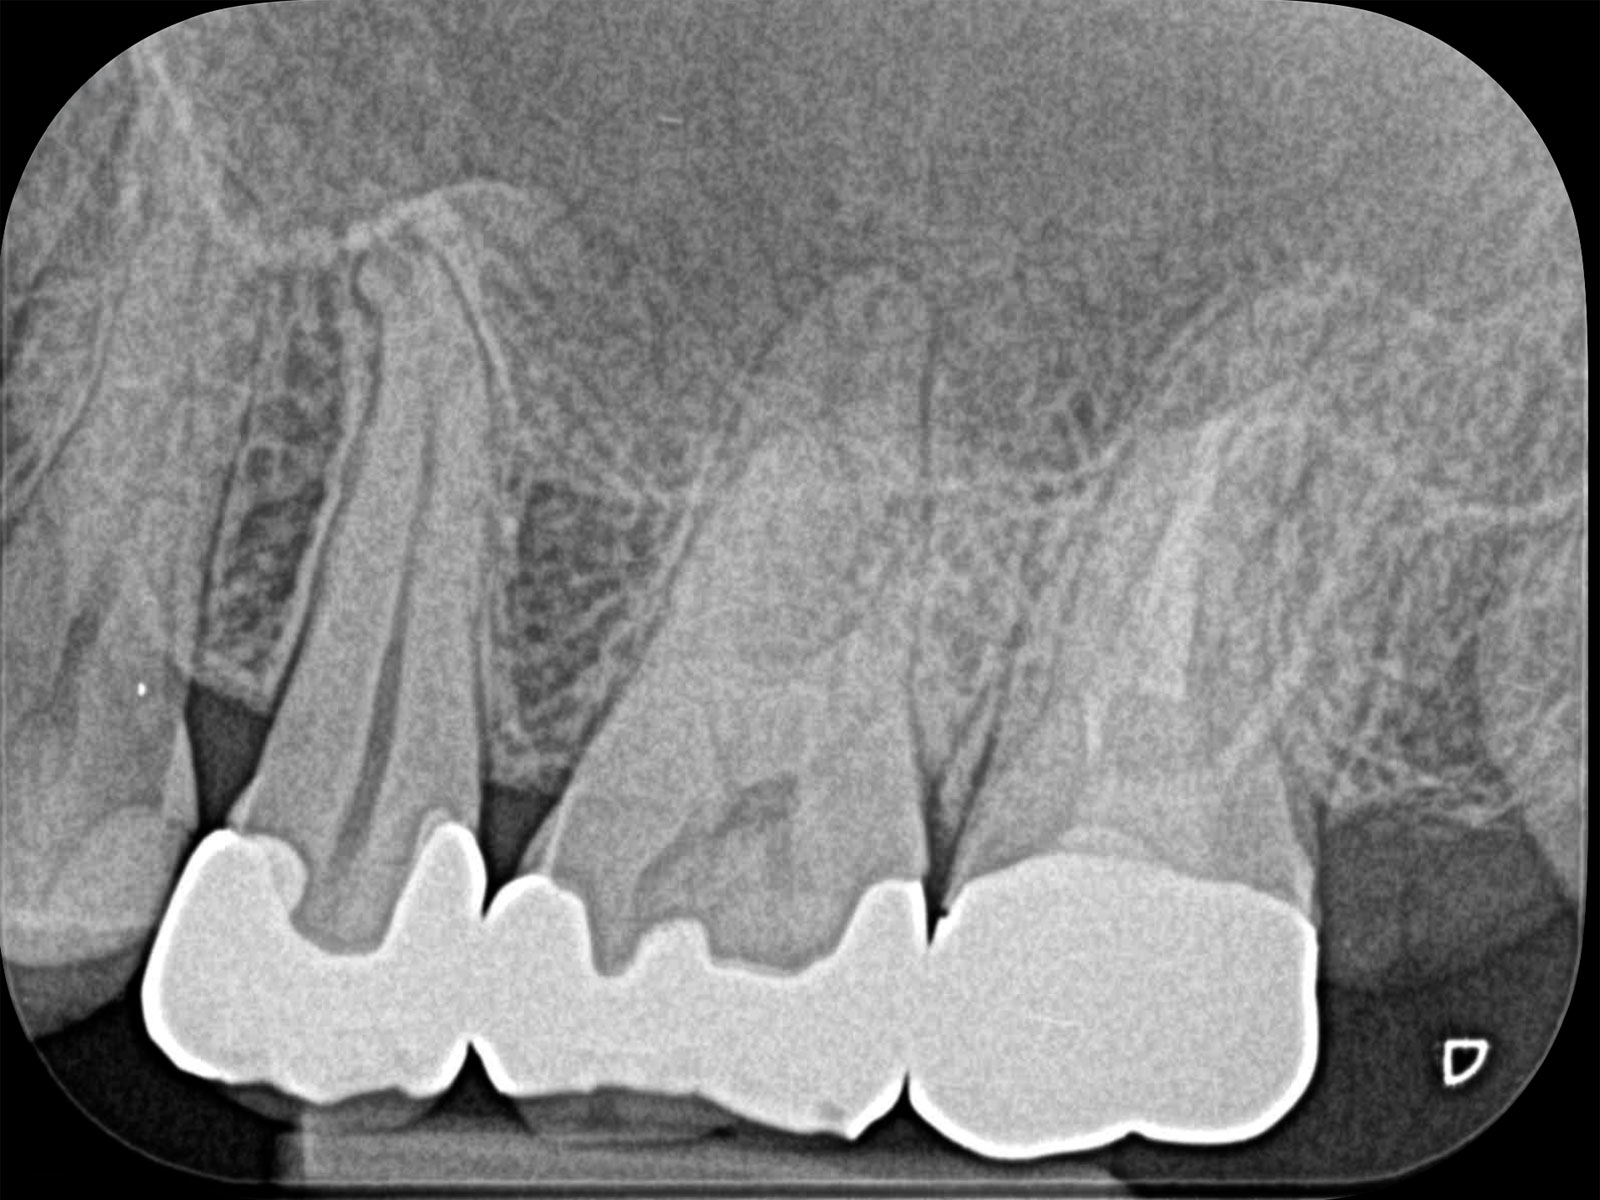

主訴: 噛むと痛い、奥歯が違和感ある

保険治療では発見することが難しい4つ目の神経を

歯を大きく削らずに見つけられます。